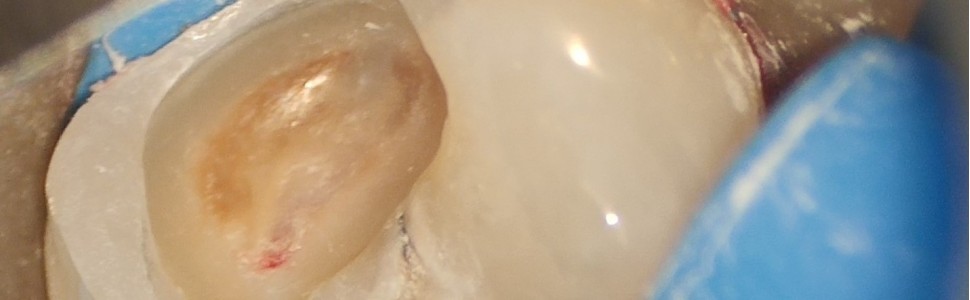

Podchloryn sodu jest obecnie najpopularniejszy środkiem do płukania kanałów korzeniowych. Najczęściej stosowany jest w postaci 1-5,25% roztworu. Poza działaniem przeciwdrobnoustrojowym i litycznym posiada także działanie wybielające, korodujące, odwaniające i hemostatyczne. NaOCl powinien być stosowany ostrożnie, ponieważ po przepchnięciu poza otwór wierzchołkowy może doprowadzić do poważnych powikłań.

Sodium hypochlorite is currently the most popular agent for root canal iriigation. It is most often used in the form of a 1-5.25% solution. In addition to antimicrobial and lytic effects, it also has bleaching, corrosive, deodorizing and hemostatic effects. NaOCl should be used with caution because if pushed beyond the apical foramen, it can lead to serious complications.